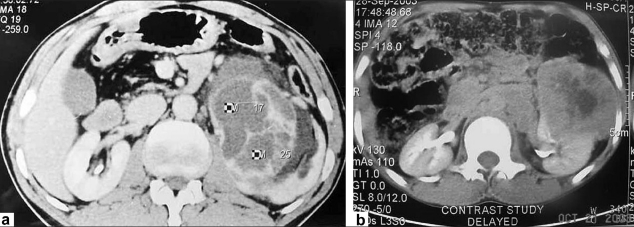

A 42-year-old male patient presented in 2001 with urinary symptoms. His physical examination was unremarkable, with normal pulse and blood pressure. Investigation at presentation revealed a normal hemogram and erythrocyte sedimentation rate (ESR). Fasting blood sugar was 90 mg/dL (normal, 90-110 mg/dL), and kidney functions were normal. Ultrasonography revealed grade one benign prostatic hyperplasia with multiple cysts in left kidney. Isotopic Renogram done after intravenous injection of 5 milli Curies of Technetium-99m diethylene triamine penta acetic acid (Tc-99m DTPA) under a large field of view Gamma camera revealed a relative renal function of 45% in left kidney and 55% in the right kidney [Figure 1]. The overall scan impression was that of an enlarged left kidney with mild functional impairment. On reevaluation in 2003, his physical examination was unremarkable. Investigations revealed a normal hemogram, normal results of kidney function tests and normal levels of serum and urinary calcium. Parathormone (PTH) levels were within normal limits. Intravenous pyelogram (IVP) revealed a well-defined cystic lesion in the left kidney near pelvicalyceal system causing splashing of pelvis, obstructed calyces and caliectasis. Contrast-enhanced CAT scan of abdomen (CECT) revealed large multiloculated cystic mass arising from left kidney, impinging on pelvis and causing hydronephrosis [Figure 2]. Fine-needle aspiration was inconclusive. Tc-99m Methylene Diphosphonate (MDP) bone scan revealed abnormal tracer uptake in multiple ribs, femur, pelvis, foot bones, tibia and 9th, 10th and 11th dorsal vertebrae [Figure 3]. Hemogram and serum chemistry were normal. Left radical nephrectomy was done in April 2003. Operative findings revealed a mass involving left kidney, with hydronephrotic changes. Histopathological examination (HPE) revealed arterial malformation of kidney [Figure 4]. Patient was referred to tertiary care center with an impression of renal cell carcinoma with diffuse bone metastasis. He was reevaluated and found to have high serum alkaline phosphatase (Alp) levels. In view of the long history, good performance status and histopathological examination, skeletal survey was done, which revealed hyperostosis of long bones, and the bone of foot resembling wax dripping on one side [Figure 5]. A final diagnosis of melorheostosis was made and the patient reassured. He is on our follow-up for the last 5 years and is asymptomatic.

| Figure 1 CECT (a,b) revealed a large multiloculated cystic mass arising from left kidney, impinging upon the pelvis and causing hydronephrosis